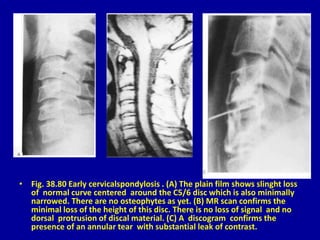

• Fig. 38.80 Early cervicalspondylosis . (A) The plain film shows slinght loss

of normal curve centered around the C5/6 disc which is also minimally

narrowed. There are no osteophytes as yet. (B) MR scan confirms the

minimal loss of the height of this disc. There is no loss of signal and no

dorsal protrusion of discal material. (C) A discogram confirms the

presence of an annular tear with substantial leak of contrast.

• Fig. 38.80 Early cervicalspondylosis . (D) cervical spondylosis in a

more advanced form. The MR scan is abnormal with anterior

discal bulging and marginal osteophytosis at C4/C5 and C5/C6

levels. (E) In the discogram of the same patient anterior and

posterior annular tears are demonstrated with dorsal bulging. The

anterior annular tears shown to extend to the osteophytes.

• Fig. 38.80Early cervicalspondylosis . (A) The plain film shows slinght loss of normal curve centered around the C5/6 disc which is also minimally narrowed. There are no osteophytes as yet. (B) MR scan confirms the minimal loss of the height of this disc. There is no loss of signal and no dorsal protrusion of discal material. (C) A discogram confirms the presence of an annular tear with substantial leak of contrast.

• Fig. 38.80Early cervicalspondylosis . (D) cervical spondylosis in a more advanced form. The MR scan is abnormal with anterior discal bulging and marginal osteophytosis at C4/C5 and C5/C6 levels. (E) In the discogram of the same patient anterior and posterior annular tears are demonstrated with dorsal bulging. The anterior annular tears shown to extend to the osteophytes.